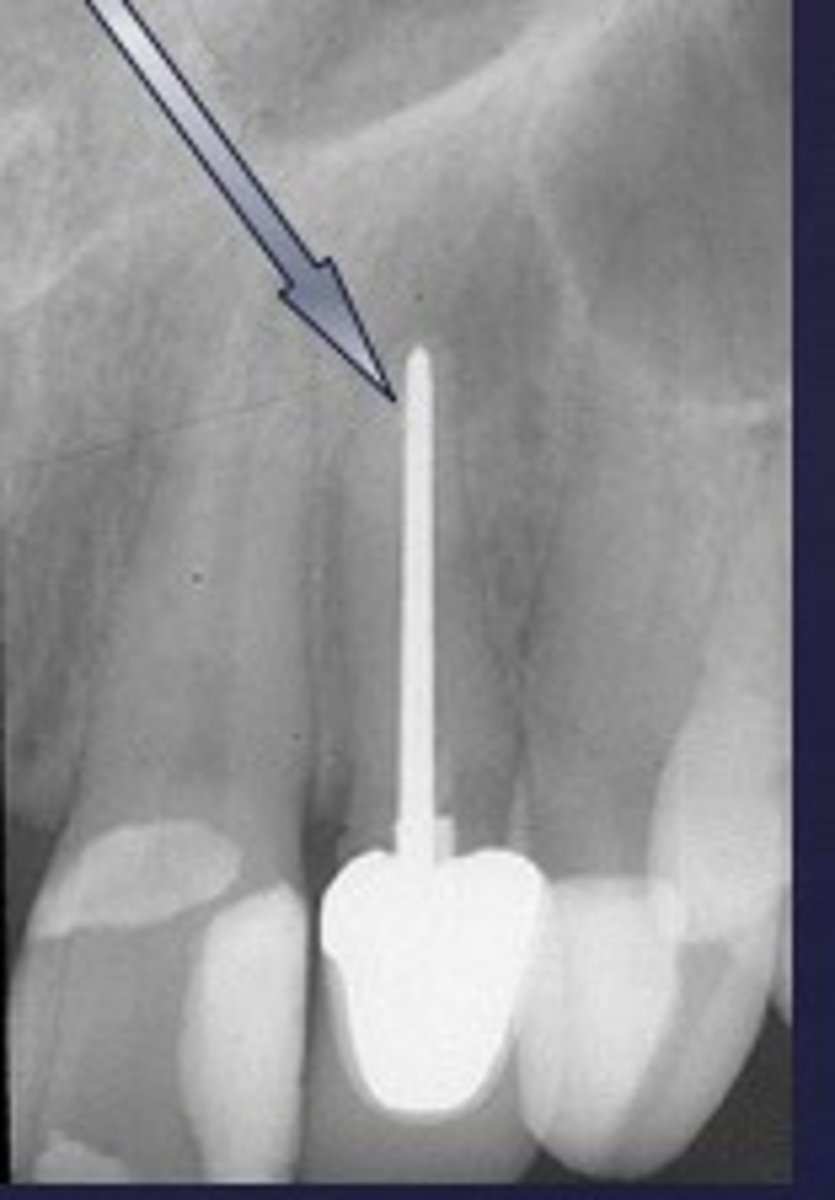

clark's rule or buccal object rule

requires 2 radiographs

all factors remain the same for the second exposure except that tube is shifted 20 degrees mesially/distally

-the buccal object will appear to have moved in the opposite direction from tube shift

-the lingual object will appear to have moved in the same direction from tube shift

SLOB

same lingual, opposite buccal